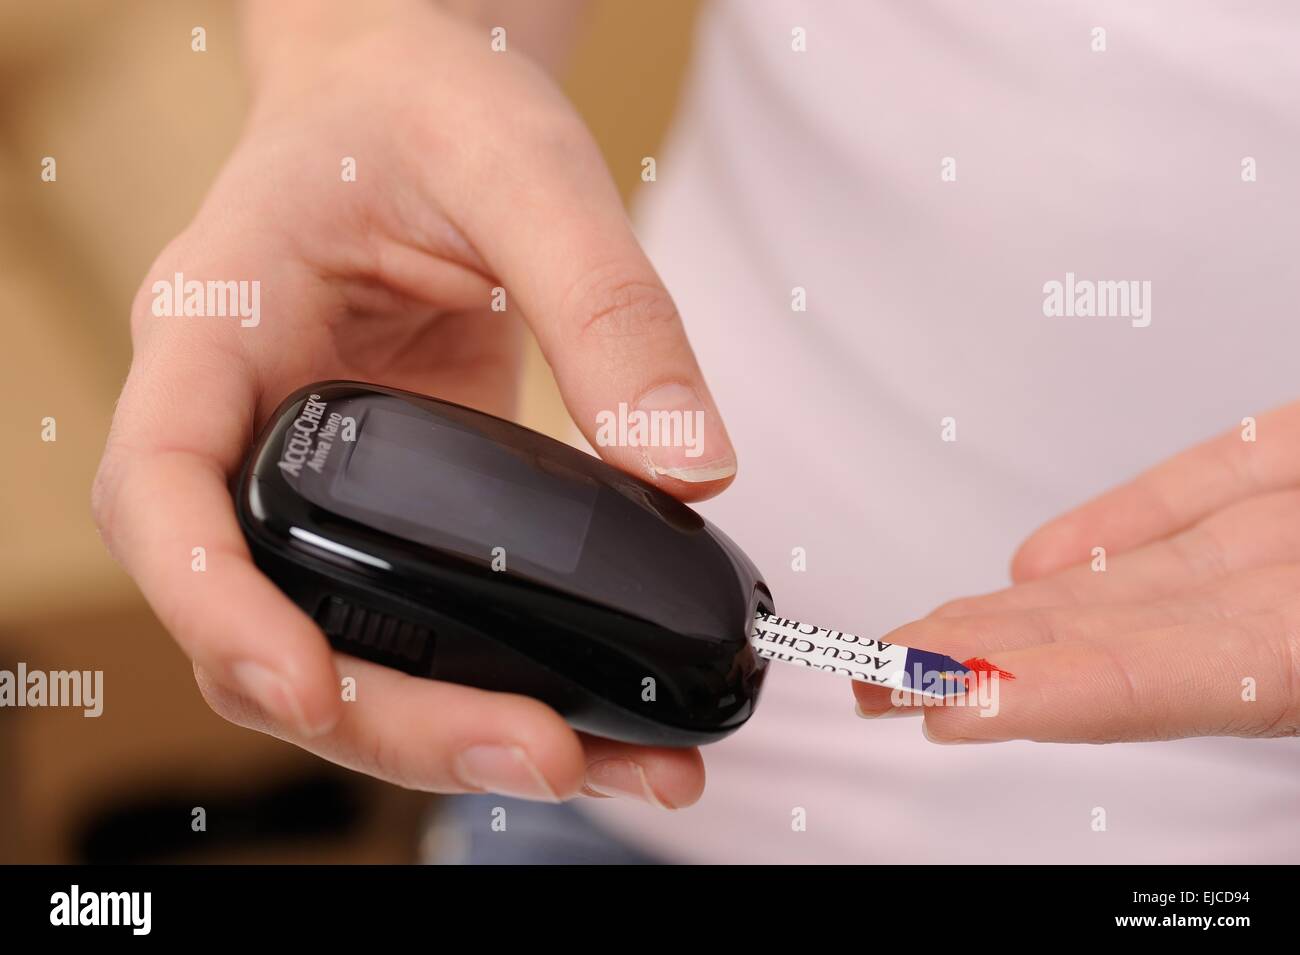

Accu chek avia nano Foto Stockhttps://www.alamy.it/image-license-details/?v=1https://www.alamy.it/foto-immagine-accu-chek-avia-nano-80179165.html

Accu chek avia nano Foto Stockhttps://www.alamy.it/image-license-details/?v=1https://www.alamy.it/foto-immagine-accu-chek-avia-nano-80179165.htmlRMEJCD9H–Accu chek avia nano

Accu chek avia nano Foto Stockhttps://www.alamy.it/image-license-details/?v=1https://www.alamy.it/foto-immagine-accu-chek-avia-nano-80179164.html

Accu chek avia nano Foto Stockhttps://www.alamy.it/image-license-details/?v=1https://www.alamy.it/foto-immagine-accu-chek-avia-nano-80179164.htmlRMEJCD9G–Accu chek avia nano

Accu chek avia nano Foto Stockhttps://www.alamy.it/image-license-details/?v=1https://www.alamy.it/foto-immagine-accu-chek-avia-nano-80179136.html

Accu chek avia nano Foto Stockhttps://www.alamy.it/image-license-details/?v=1https://www.alamy.it/foto-immagine-accu-chek-avia-nano-80179136.htmlRMEJCD8G–Accu chek avia nano

Accu chek avia nano Foto Stockhttps://www.alamy.it/image-license-details/?v=1https://www.alamy.it/foto-immagine-accu-chek-avia-nano-80179160.html

Accu chek avia nano Foto Stockhttps://www.alamy.it/image-license-details/?v=1https://www.alamy.it/foto-immagine-accu-chek-avia-nano-80179160.htmlRMEJCD9C–Accu chek avia nano

Accu chek avia nano Foto Stockhttps://www.alamy.it/image-license-details/?v=1https://www.alamy.it/foto-immagine-accu-chek-avia-nano-80179161.html

Accu chek avia nano Foto Stockhttps://www.alamy.it/image-license-details/?v=1https://www.alamy.it/foto-immagine-accu-chek-avia-nano-80179161.htmlRMEJCD9D–Accu chek avia nano

Accu chek avia nano Foto Stockhttps://www.alamy.it/image-license-details/?v=1https://www.alamy.it/foto-immagine-accu-chek-avia-nano-80179140.html

Accu chek avia nano Foto Stockhttps://www.alamy.it/image-license-details/?v=1https://www.alamy.it/foto-immagine-accu-chek-avia-nano-80179140.htmlRMEJCD8M–Accu chek avia nano

Accu chek avia nano Foto Stockhttps://www.alamy.it/image-license-details/?v=1https://www.alamy.it/foto-immagine-accu-chek-avia-nano-80179152.html

Accu chek avia nano Foto Stockhttps://www.alamy.it/image-license-details/?v=1https://www.alamy.it/foto-immagine-accu-chek-avia-nano-80179152.htmlRMEJCD94–Accu chek avia nano

Accu chek avia nano Foto Stockhttps://www.alamy.it/image-license-details/?v=1https://www.alamy.it/foto-immagine-accu-chek-avia-nano-80179149.html

Accu chek avia nano Foto Stockhttps://www.alamy.it/image-license-details/?v=1https://www.alamy.it/foto-immagine-accu-chek-avia-nano-80179149.htmlRMEJCD91–Accu chek avia nano